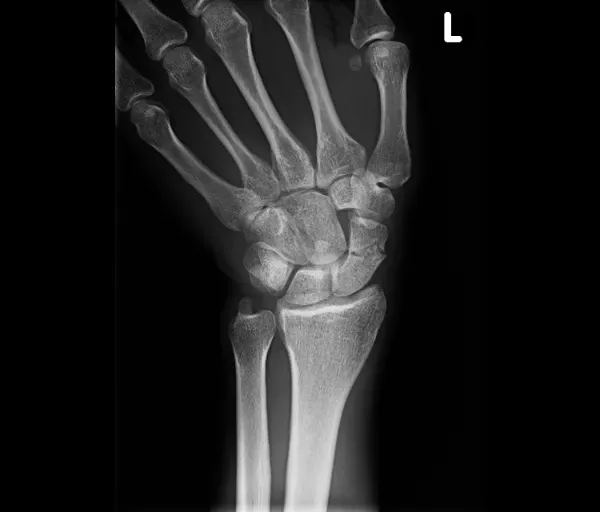

Scaphoidfractuur

Wat is het?

Het scaphoid is een handwortelbeentje aan de duimzijde van de pols. Een breuk ontstaat meestal door een val op de hand. Scaphoidbreuken geven soms weinig klachten, waardoor ze gemakkelijk gemist worden. Het scaphoid heeft een zwakke bloedvoorziening, vooral in de proximale pool. Hierdoor is er risico op:

- non-union/pseudartrose (breuk groeit niet aan elkaar)

- en hierdoor later artrose van de pols (SNAC-wrist)

Operatief

Nodig bij:

- Proximale poolfracturen (slechte bloedvoorziening)

- Verplaatste breuken

- Non-union of malunion

Behandelingen:

- Schroeffixatie: vergroot de kans op genezing en verkort de gipsperiode

- Percutane techniek voor recente, niet-verplaatste breuken (klein sneetje)

- Open ingreep voor verplaatste breuken

- Bij non-union/malunion: aanvulling met botgreffe uit het bekken of het spaakbeen